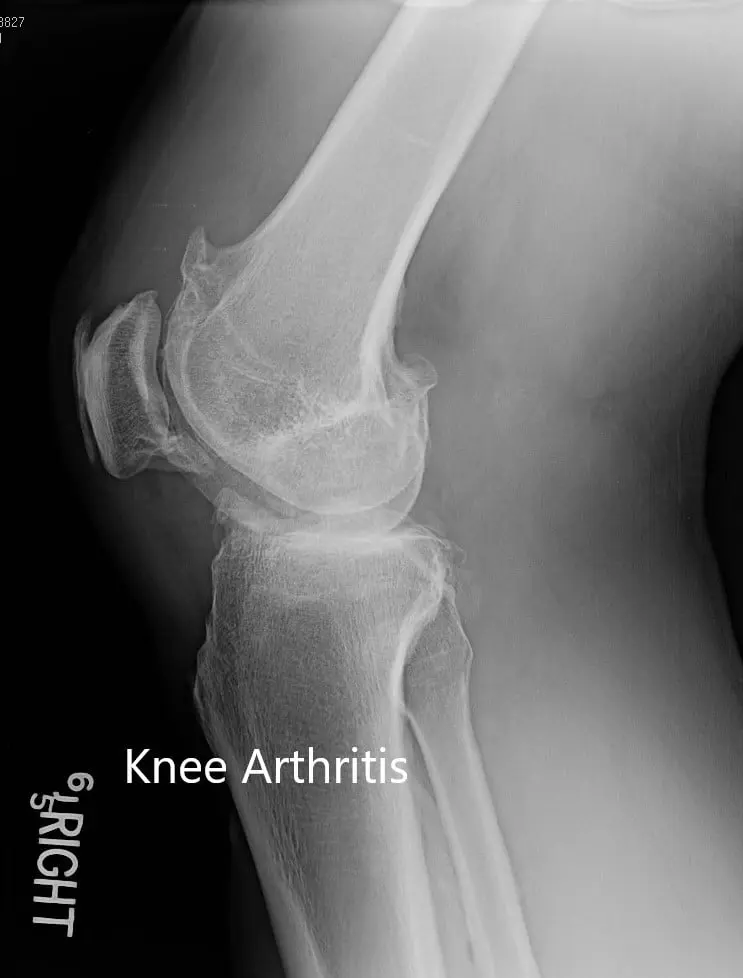

Imaging studies revealed severe tricompartmental osteoarthritis of the right knee. Considering the lifestyle limiting knee pain, the patient was advised right total knee replacement. All the risks, benefits and alternatives were discussed in detail with the patient. The patient agreed to go ahead with the procedure.

Preoperative X-ray of the right knee in lateral view and skyline view.